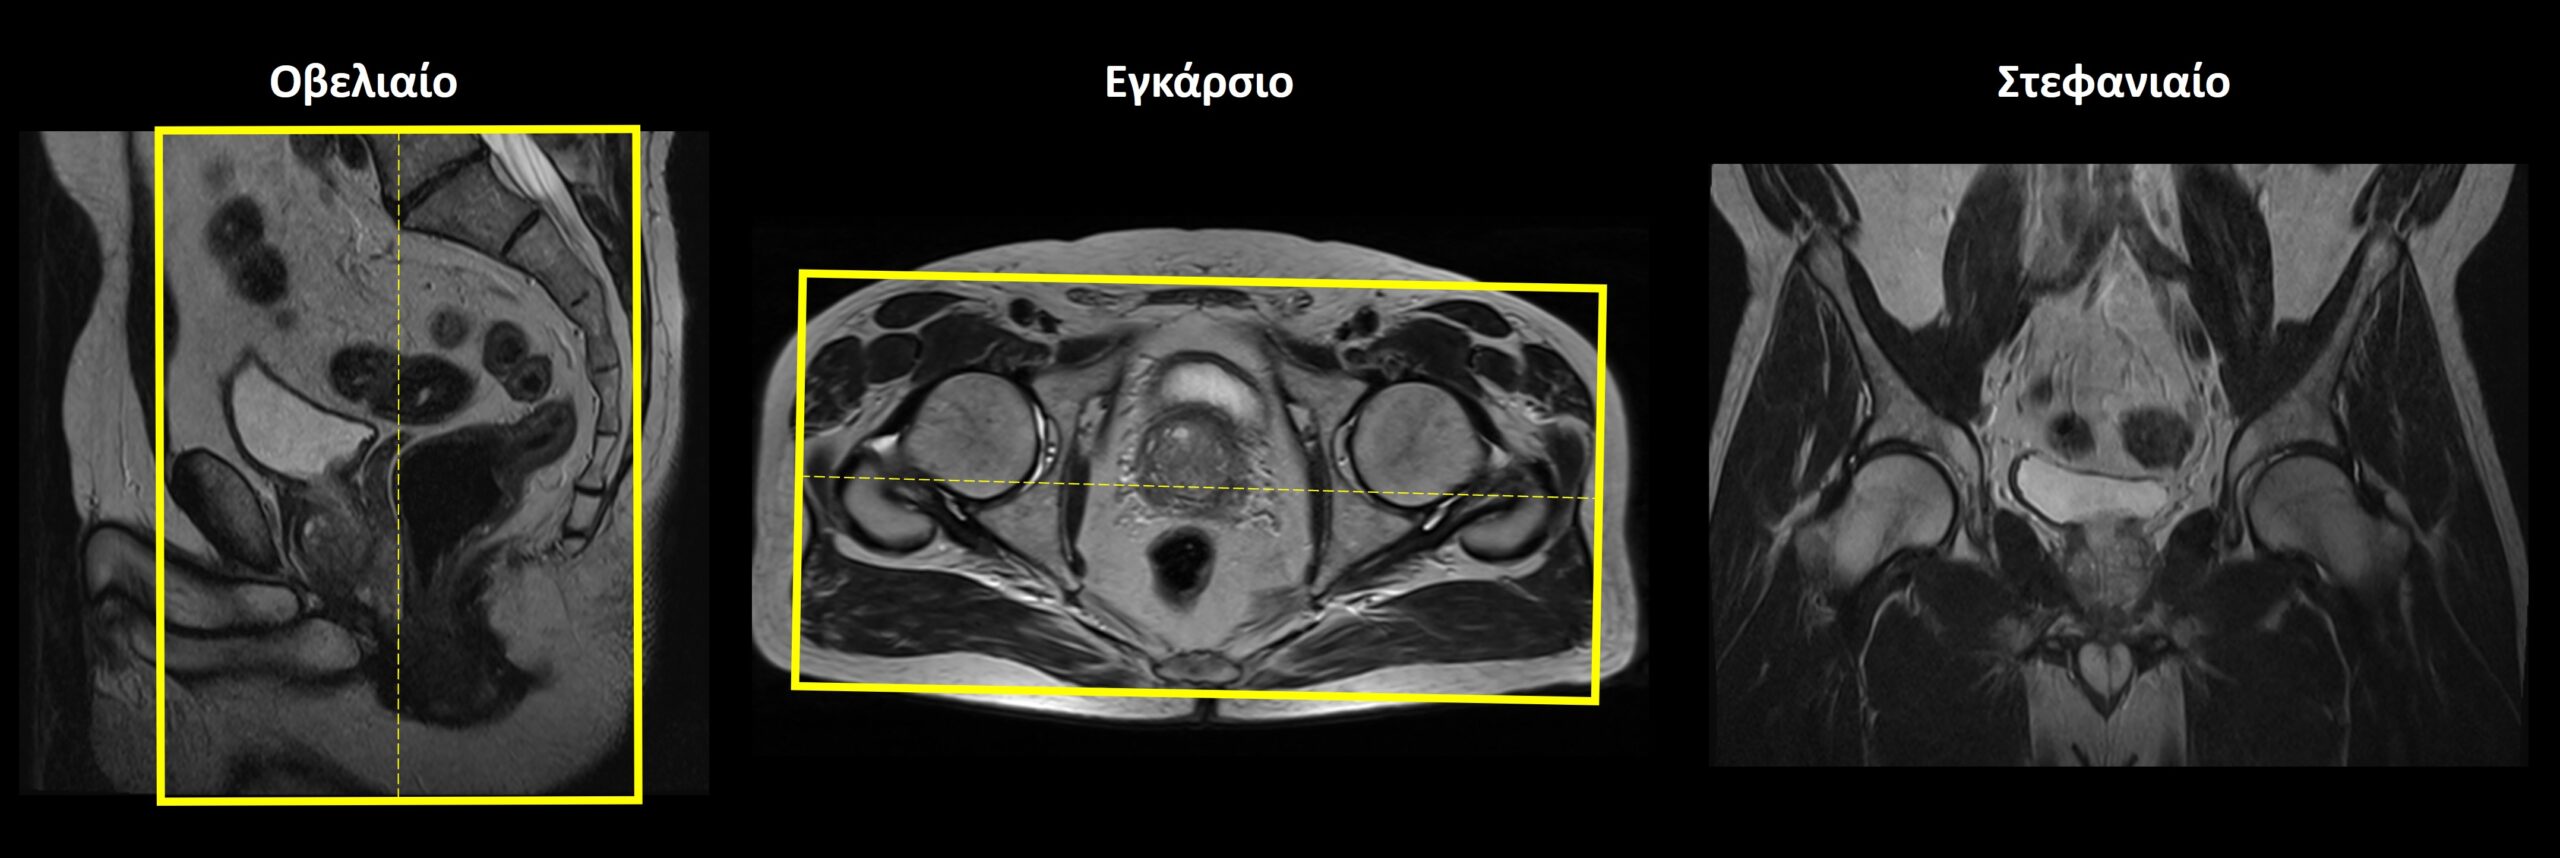

Οβελιαίο επίπεδο (Sagittal): οι οβελιαίες τομές σχεδιάζονται κατά μήκος των οργάνων της πυέλου τόσο στο εγκάρσιο όσο και στο στεφανιαίο επίπεδο. Η κλίση των τομών στο εγκάρσιο επίπεδο πρέπει να είναι παράλληλη με τη νοητή γραμμή που ενώνει την ηβική σύμφυση με τον πρωκτικό σωλήνα. Κατάλληλη κλίση πρέπει να δοθεί και στο στεφανιαίο επίπεδο, παράλληλα με το ορθό και τον πρωκτικό σωλήνα. Οι τομές πρέπει να περιλαμβάνουν τα όργανα της πυέλου, από την δεξιά έως την αριστερή κοτύλη.

Εγκάρσιο (Axial/Transversal): οι εγκάρσιες τομές σχεδιάζονται παράλληλα με τις κεφαλές των μηριαίων στο στεφανιαίο επίπεδο και κάθετα στονπρωκτικό σωλήνα στο οβελιαίο επίπεδο. Οι τομές πρέπει να περιλαμβάνουν τα όργανα της πυέλου, από τις λαγόνιες ακρολοφίες (πάνω) έως τον πρωκτό (κάτω).

• Οβελιαίο επίπεδο (Sagittal): χρήση μίας μοναδικής τομής πάχους 10-15 mm, η οποία σχεδιάζεται παράλληλα με το ορθό και τον πρωκτικό σωλήνα στο στεφανιαίο επίπεδο. Κατάλληλη κλίση πρέπει να δοθεί και στο εγκάρσιο επίπεδο, παράλληλα με τη νοητή γραμμή που ενώνει την ηβική σύμφυση με τον πρωκτικό σωλήνα. Επίσης, η τομή πρέπει να τοποθετηθεί στη μέση του ορθού και του πρωκτού.